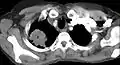

Tomografía computada que muestra un tumor de Pancoast (etiquetado como P, carcinoma pulmonar de células grandes, pulmón derecho), de una mujer fumadora de 47 años.